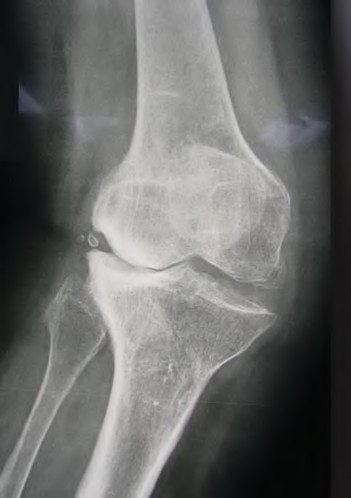

A 65-year-old woman with painful knee arthritis and the deformity seen in Figure A, is scheduled to undergo a total knee arthroplasty. All the following are risk factors for a post-operative peroneal palsy EXCEPT:

Figure A demonstrates and AP radiograph of the knee showing end-stage arthritis with severe lateral compartment narrowing.